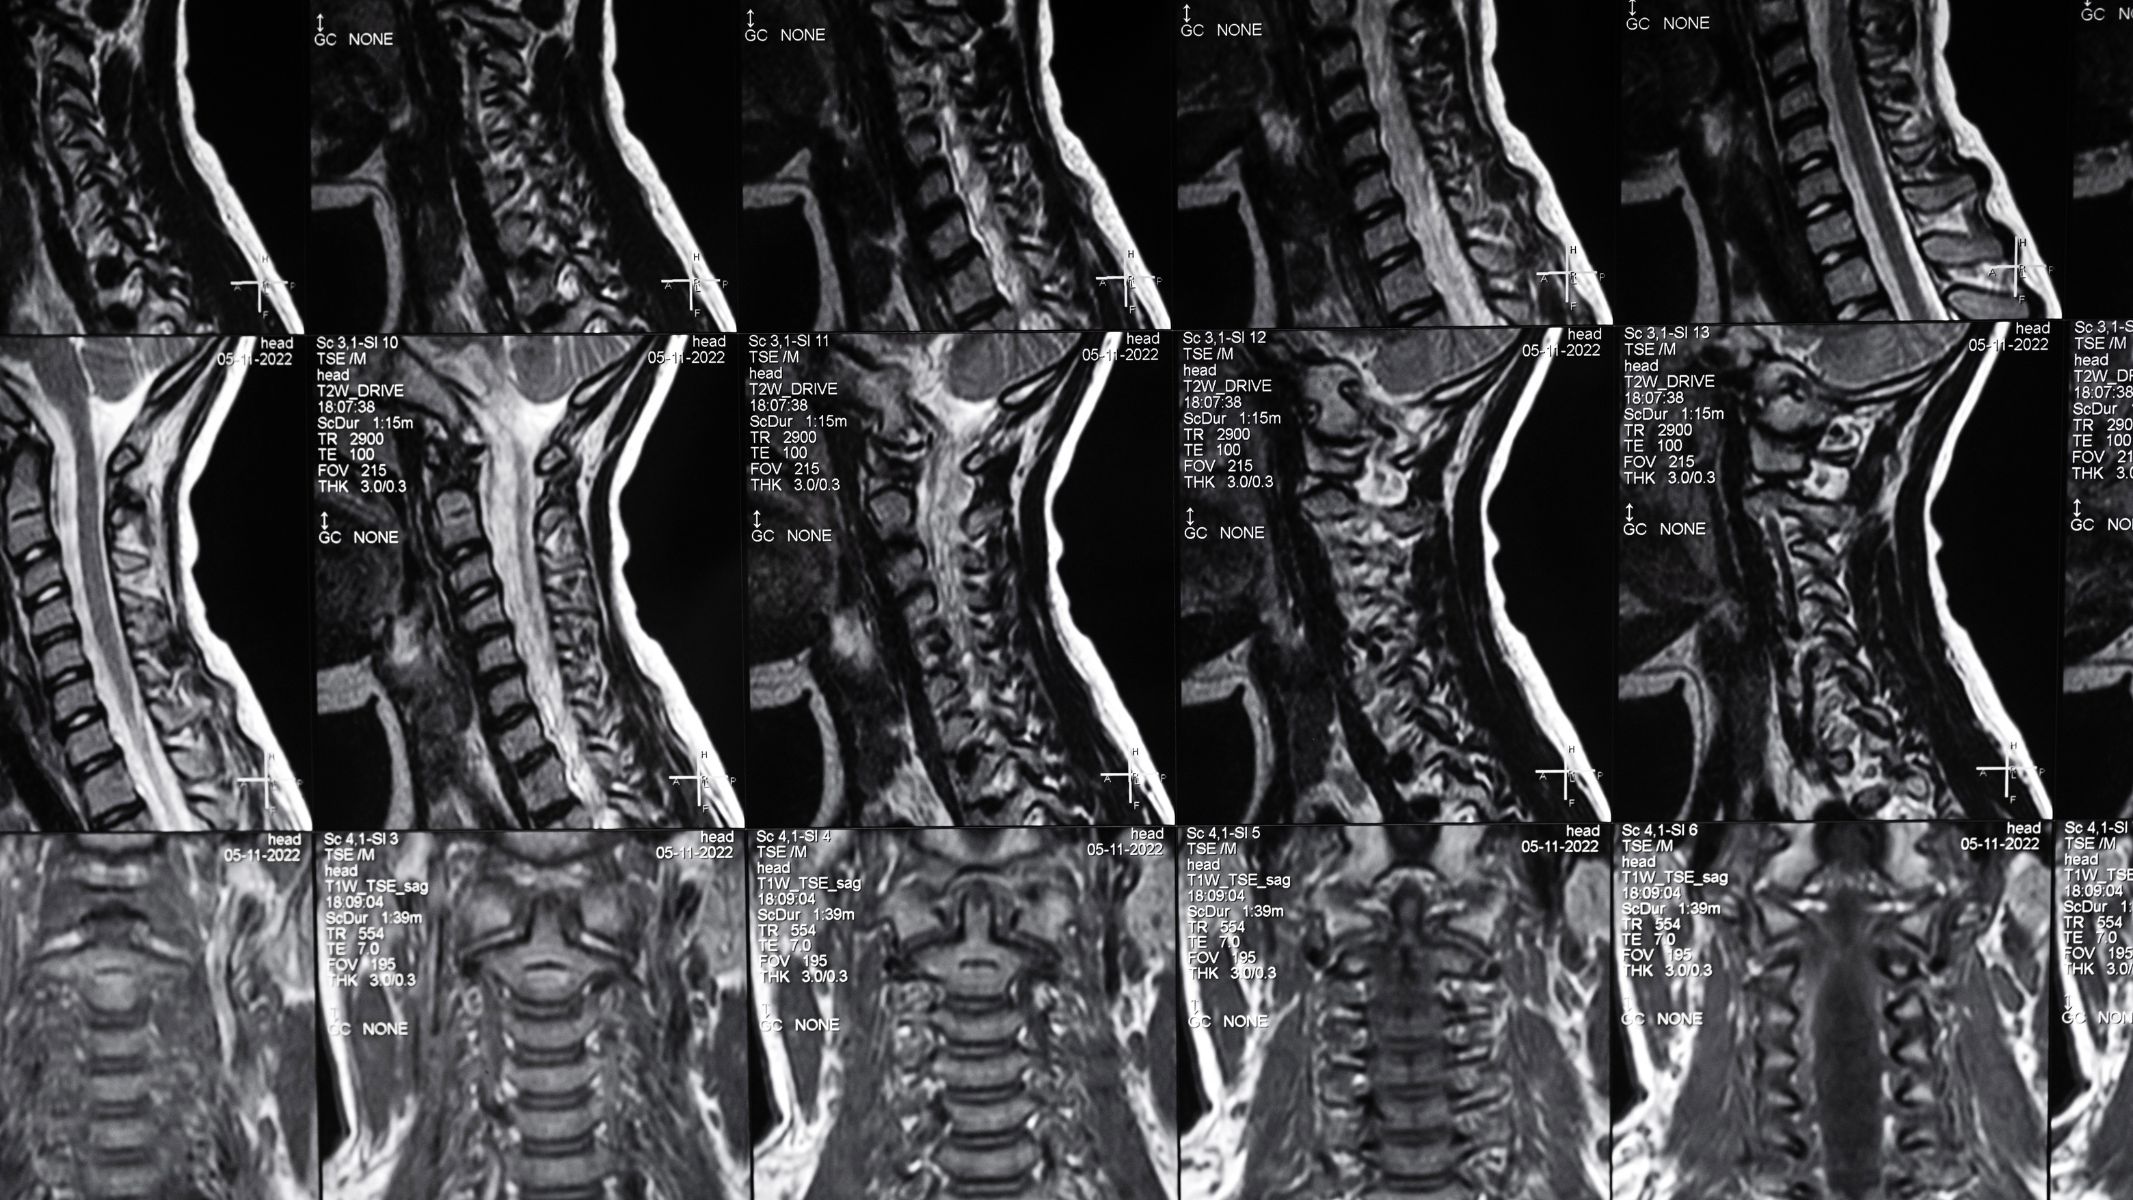

MRI cột sống cổ là kỹ thuật chẩn đoán hình ảnh hiện đại sử dụng từ trường mạnh và sóng radio để tạo ra hình ảnh chi tiết của cột sống cổ. Phương pháp này cho phép quan sát rõ các cấu trúc như đốt sống, đĩa đệm, tủy sống, rễ thần kinh và các mô mềm xung quanh.

Khác với chụp X-quang hay CT, MRI có khả năng đánh giá mô mềm vượt trội. Nhờ đó, những tổn thương sớm ở đĩa đệm hoặc dây thần kinh có thể được phát hiện ngay cả khi chưa gây biến dạng xương rõ rệt. Đây là lợi thế lớn trong việc chẩn đoán các bệnh lý cột sống cổ giai đoạn đầu.

Trong thực hành lâm sàng, MRI cột sống cổ thường được sử dụng để phát hiện và theo dõi các tình trạng như thoát vị đĩa đệm cột sống cổ, thoái hóa cột sống cổ, hẹp ống sống, chèn ép tủy sống, viêm cột sống, chấn thương vùng cổ hoặc các khối u. Kết quả MRI cung cấp thông tin quan trọng giúp bác sĩ đánh giá mức độ tổn thương và xây dựng phác đồ điều trị phù hợp.